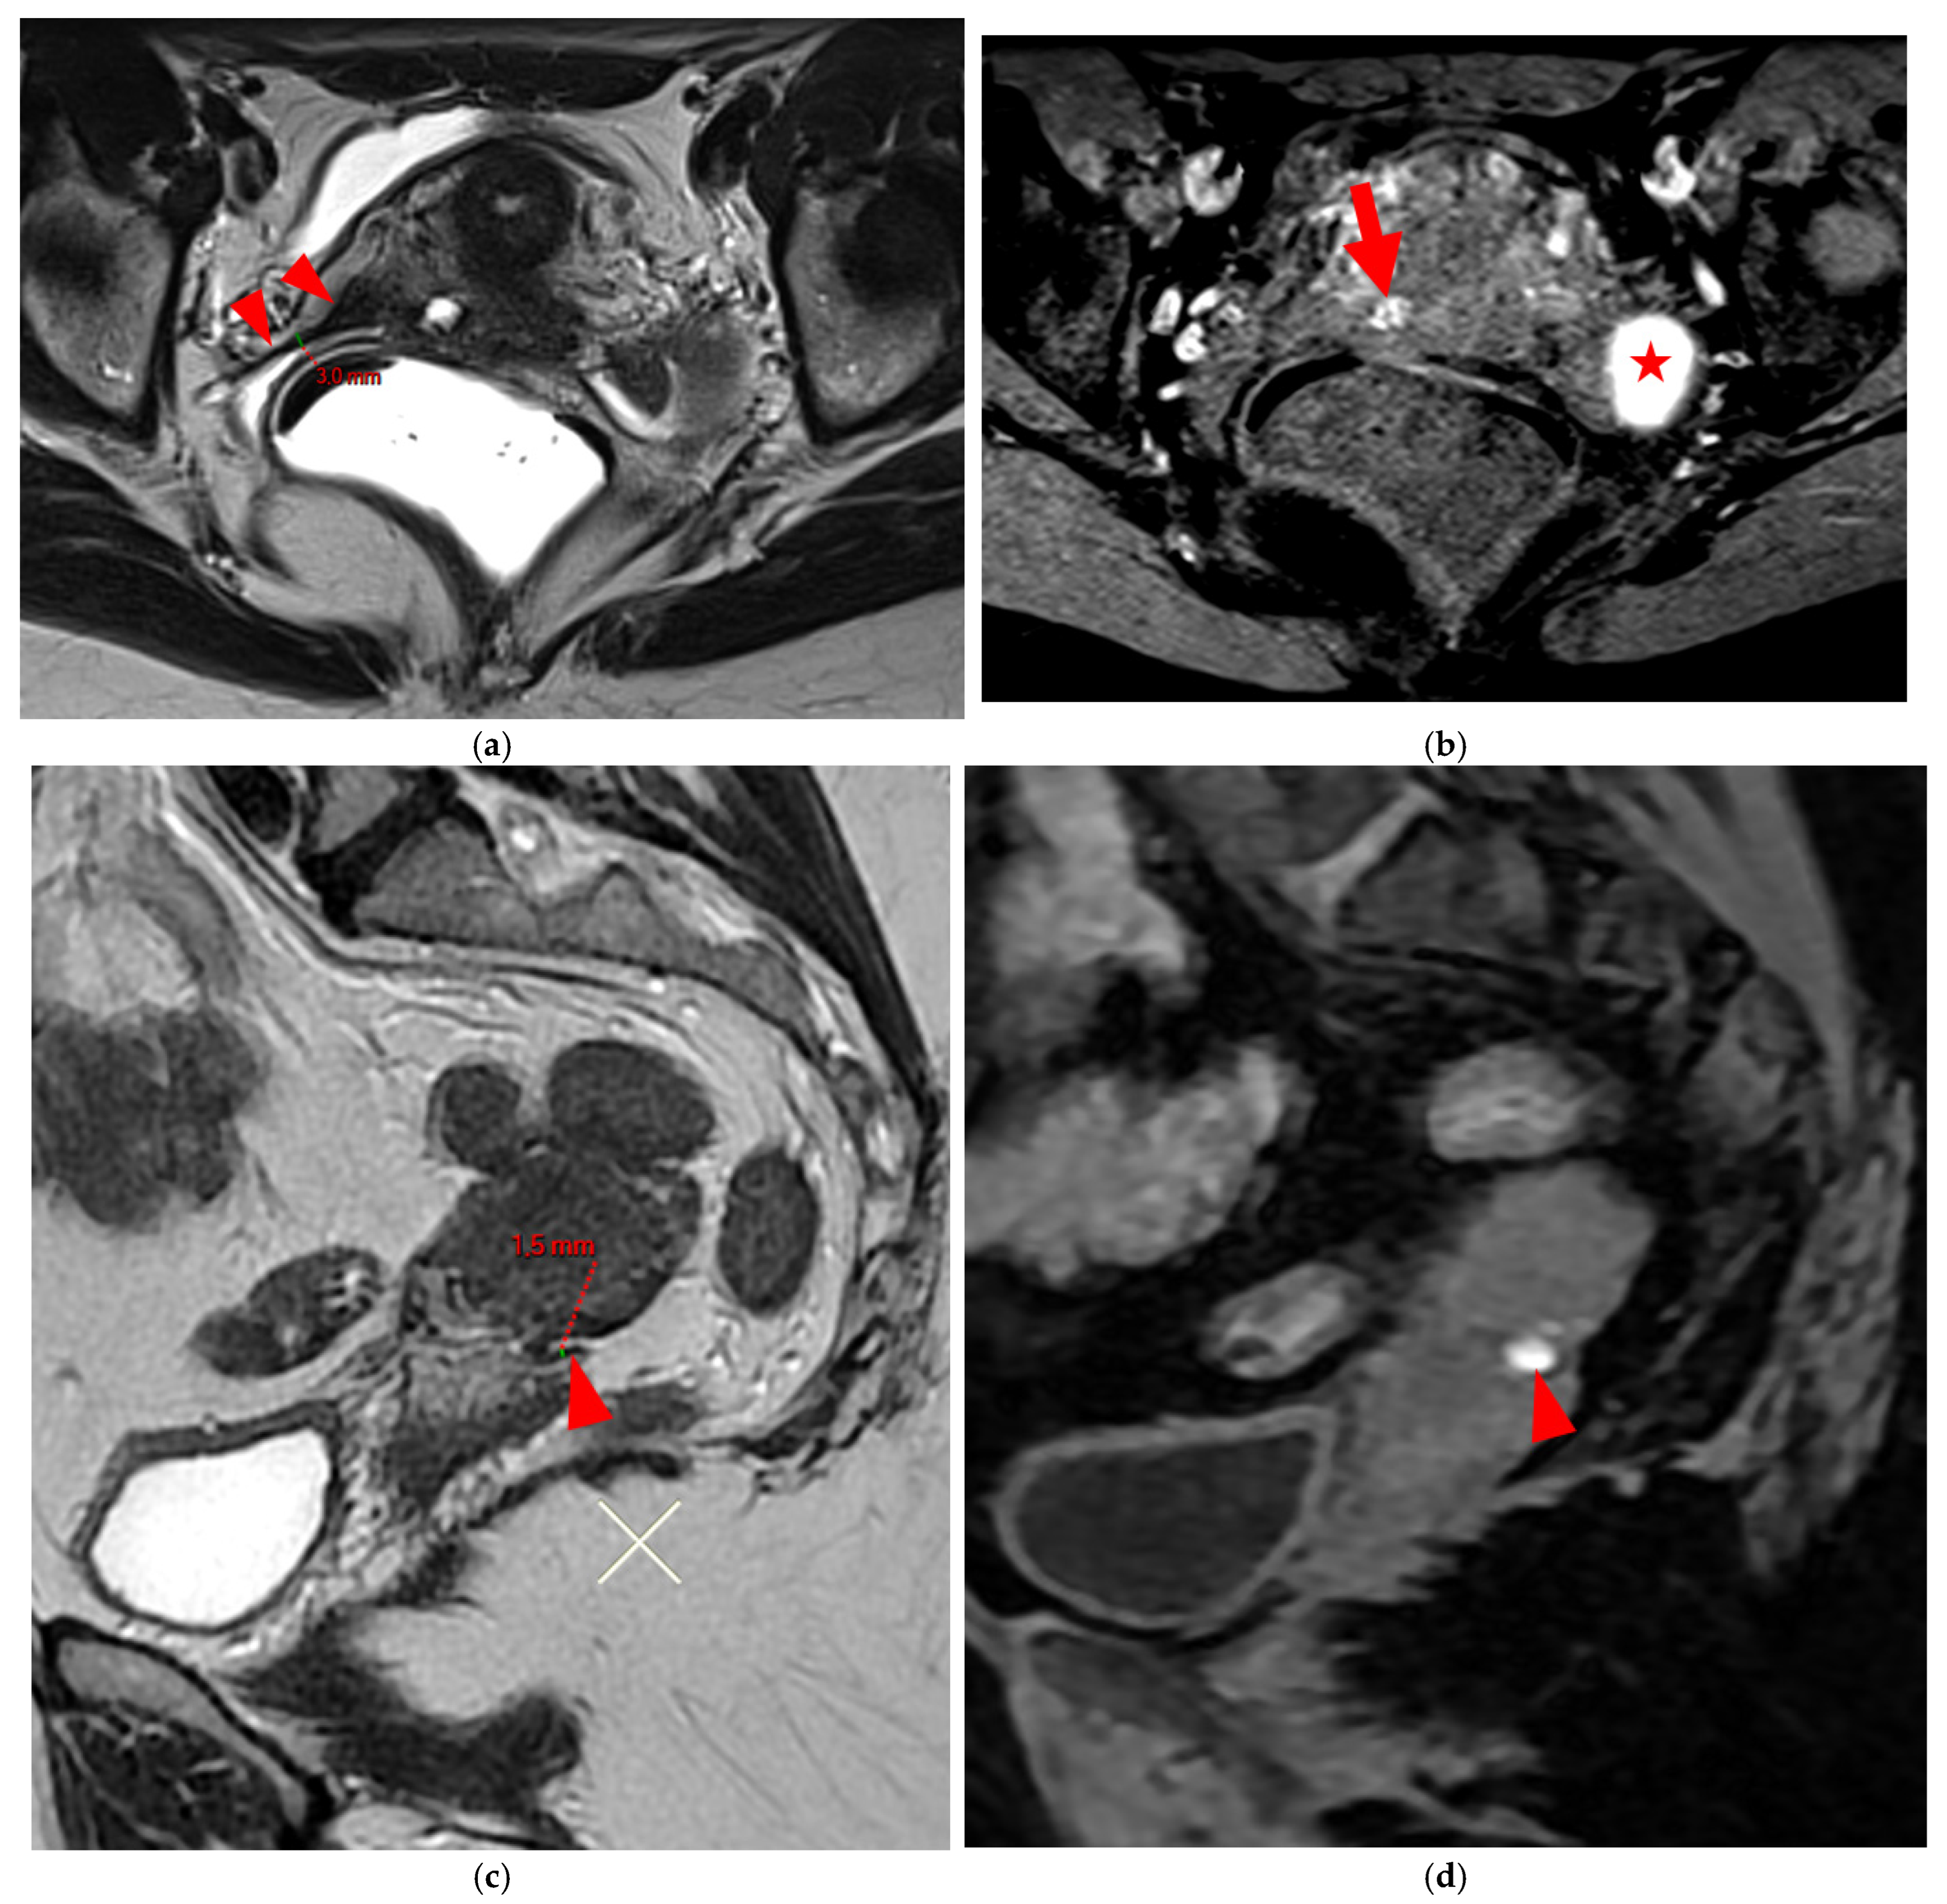

2.2.1. HTD Type 4 USL (PPV = 100%; FPR = 0%)

A type 4 USL (Figure 5) contains hemorrhagic implants, visible on MRI as hyperintense spots on fat-suppressed T1WI.

Figure 5. Pelvic MRI scans of two patients with HTD type 4 USLs. (a,b) Patient 1—(a) Axial T2WI: a focally thickened right proximal USL (arrowhead) with caliber disparity, initially classified as a type 3B USL. (b) Axial fat-suppressed T1WI: a hyperintense hemorrhagic spot (arrowhead) within this thickened right proximal USL, ultimately reclassifying it as a type 4 USL. Note the typical hyperintense right ovarian endometrioma (red star). (c,d) Patient 2—(c) Sagittal T2WI: a visible but thin (1.5 mm) left USL (arrowhead), initially classified as a type 2 USL. (d) Sagittal fat-suppressed T1WI: a hyperintense hemorrhagic spot (arrowhead) at the origin of this USL, ultimately reclassifying it as a type 4 USL.